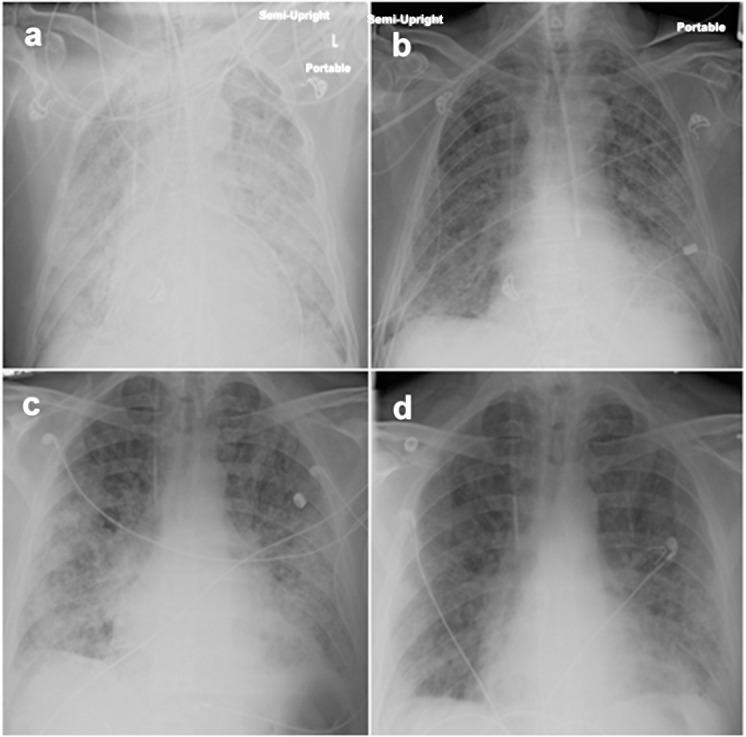

Nine (9) trial subjects (82%) had improvements of pulmonary gas exchange after treatment, compared to one (5%) historical control. Two of the three trial subjects who relapsed after only five TPE responded again with additional TPE. The three latest subjects who responded to an augmented regimen of nine TPE plus rituximab plus IVIG have had sustained responses without relapses after 96-to-237 days. Anti-HEp-2 autoantibodies were present in trial subjects prior to therapy, and were reduced by TPE among those who responded to treatment. Conversely, plasma MMP7 levels were not systematically affected by therapy nor correlated with clinical responses. One-year survival of trial subjects was 46+15% vs. 0% among historical controls. No serious adverse events were attributable to the experimental medications.

9例(82%)试验受试者在治疗后肺气体交换有改善,相比之下历史对照中有1例(5%)有改善。仅接受5次TPE后复发的3例试验受试者中有2例再次接受额外TPE后有反应。对9次TPE加利妥昔单抗加IVIG的强化方案有反应的3例最新受试者在96至237天后有持续反应且未复发。试验受试者在治疗前存在抗HEp-2自身抗体,治疗有反应者中TPE使其减少。相反,血浆MMP7水平未受到治疗的系统性影响,也与临床反应无关。试验受试者的1年生存率为46±15%,而历史对照为0%。没有严重不良事件可归因于试验药物。